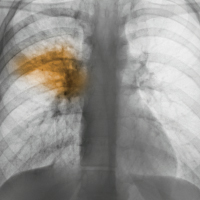

Before antibiotics, treating pneumonia (shown in this colorized X-ray) was a varied affair — but the approaches weren’t unscientific.

Credit: Scott Camazine/Visuals Unlimited